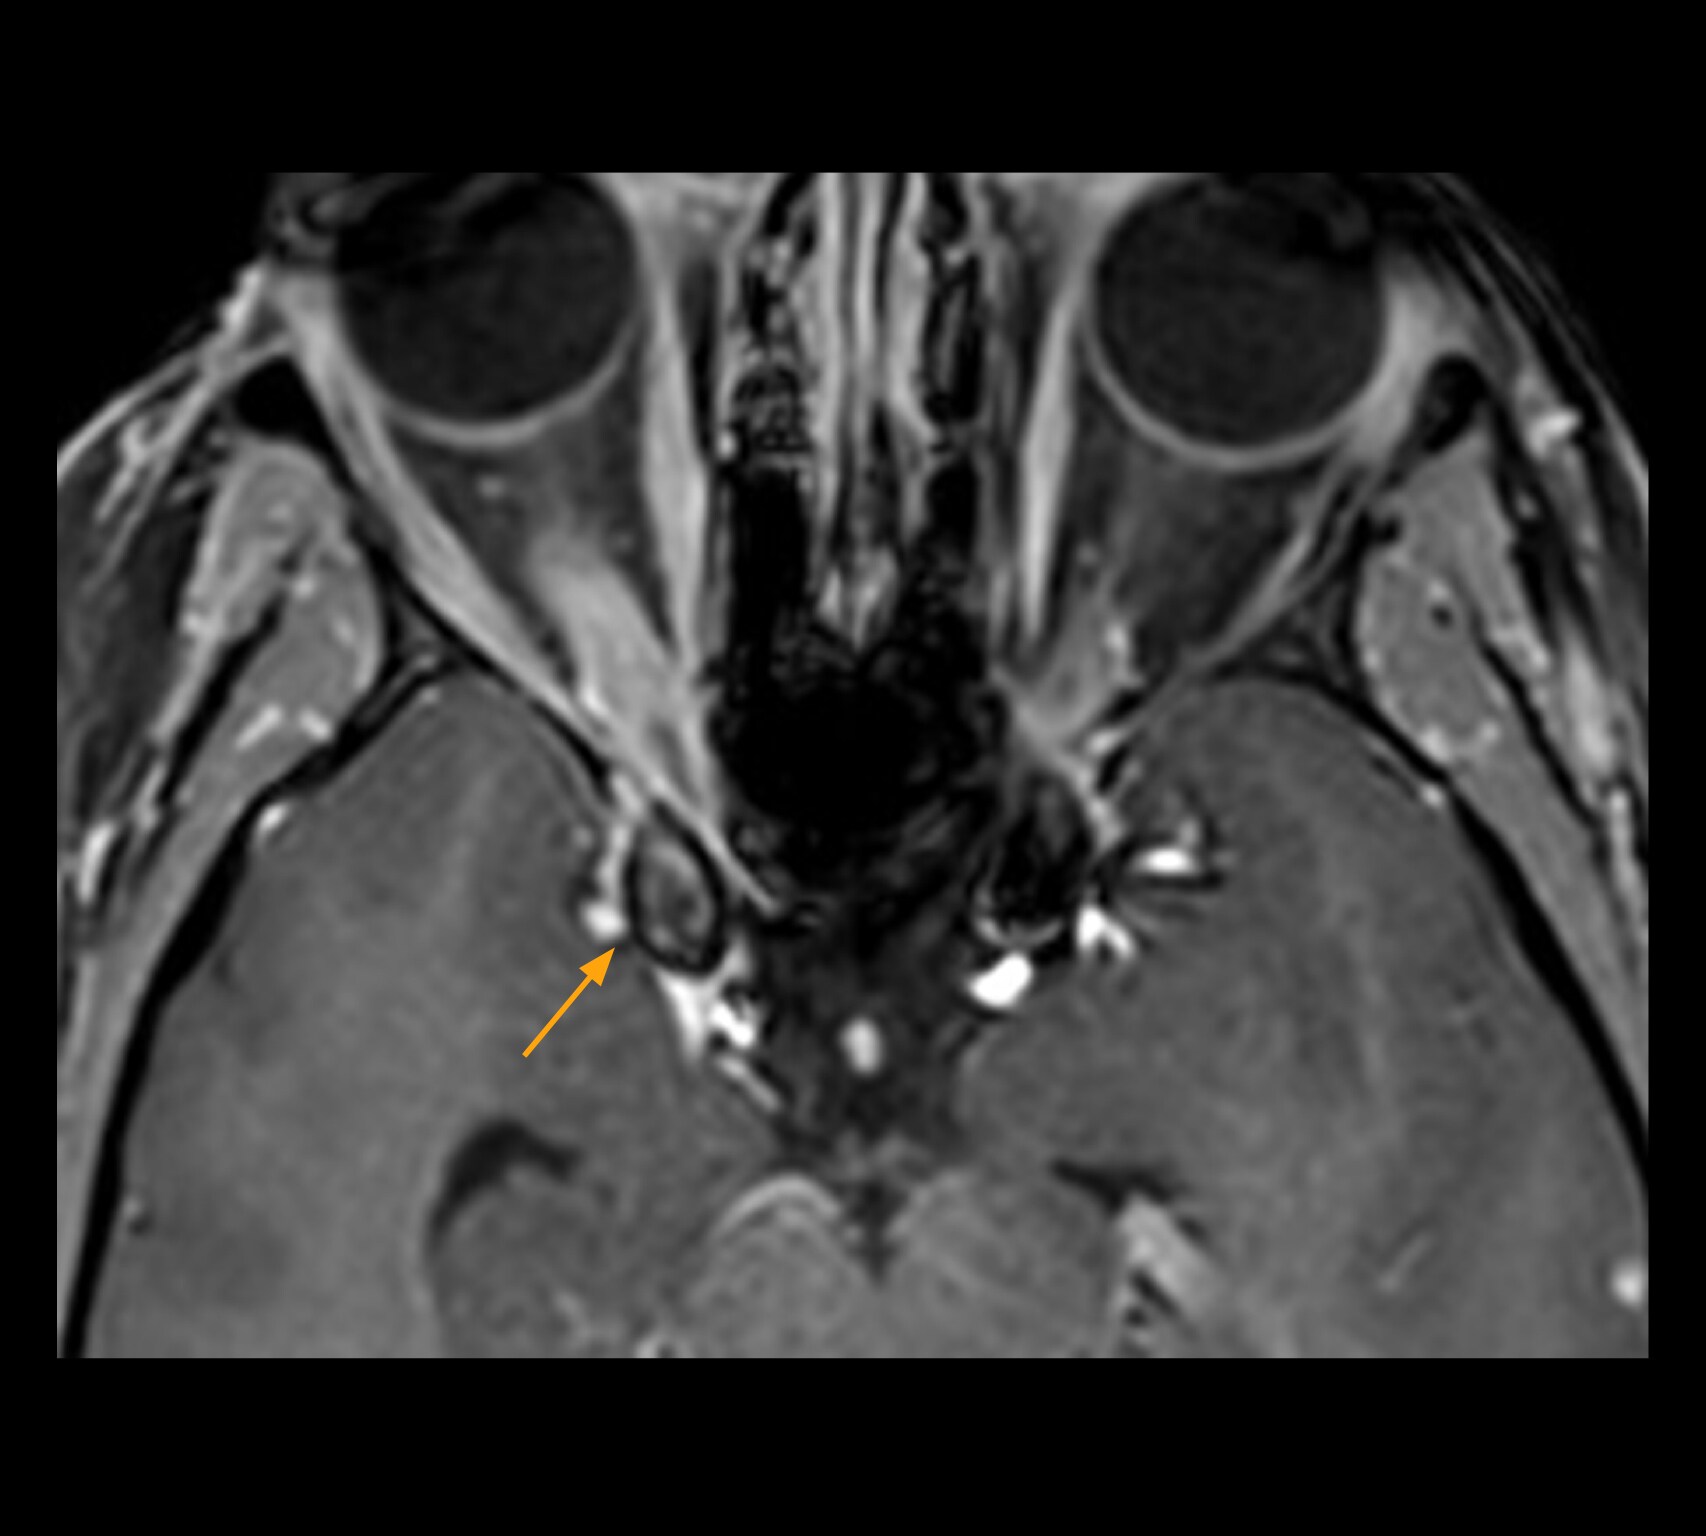

The images below show how high resolution-MRI impressively demonstrates the compression and narrowing of the right optic nerve in this case of optic nerve sheath meningioma (ONSM). The coronal T2-weighted images show the hyper-intense, half-moon shaped lesion, that is clearly visible in the axial T1W image after contrast injection (right). These imaging findings were so convincing that the responsible neurosurgeon did not consider a pretherapeutic histological clarification.

MRI of optic nerve sheath meningioma (ONSM). The coronal T2-weighted images show the hyper-intense, half-moon shaped lesion, that is clearly visible post contrast in the axial T1W (right).